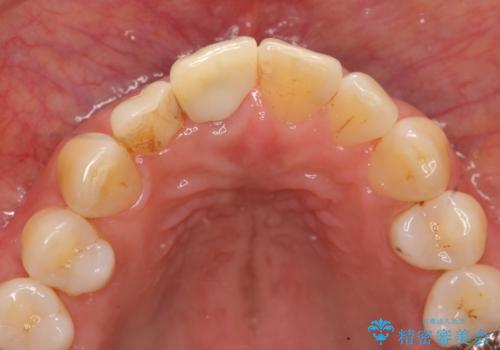

前歯 インプラントによる欠損補綴

- 目立つ一番前の歯を失い、接着剤で応急処置をしていましたが永続性のある修復を希望され来院されました。

入れ歯・ブリッジ・インプラントによる欠損補綴の方法のうち審美的で取り外しがなく隣の歯を削らない治療を望まれたため、インプラントによる審美・機能回復治療を計画します。